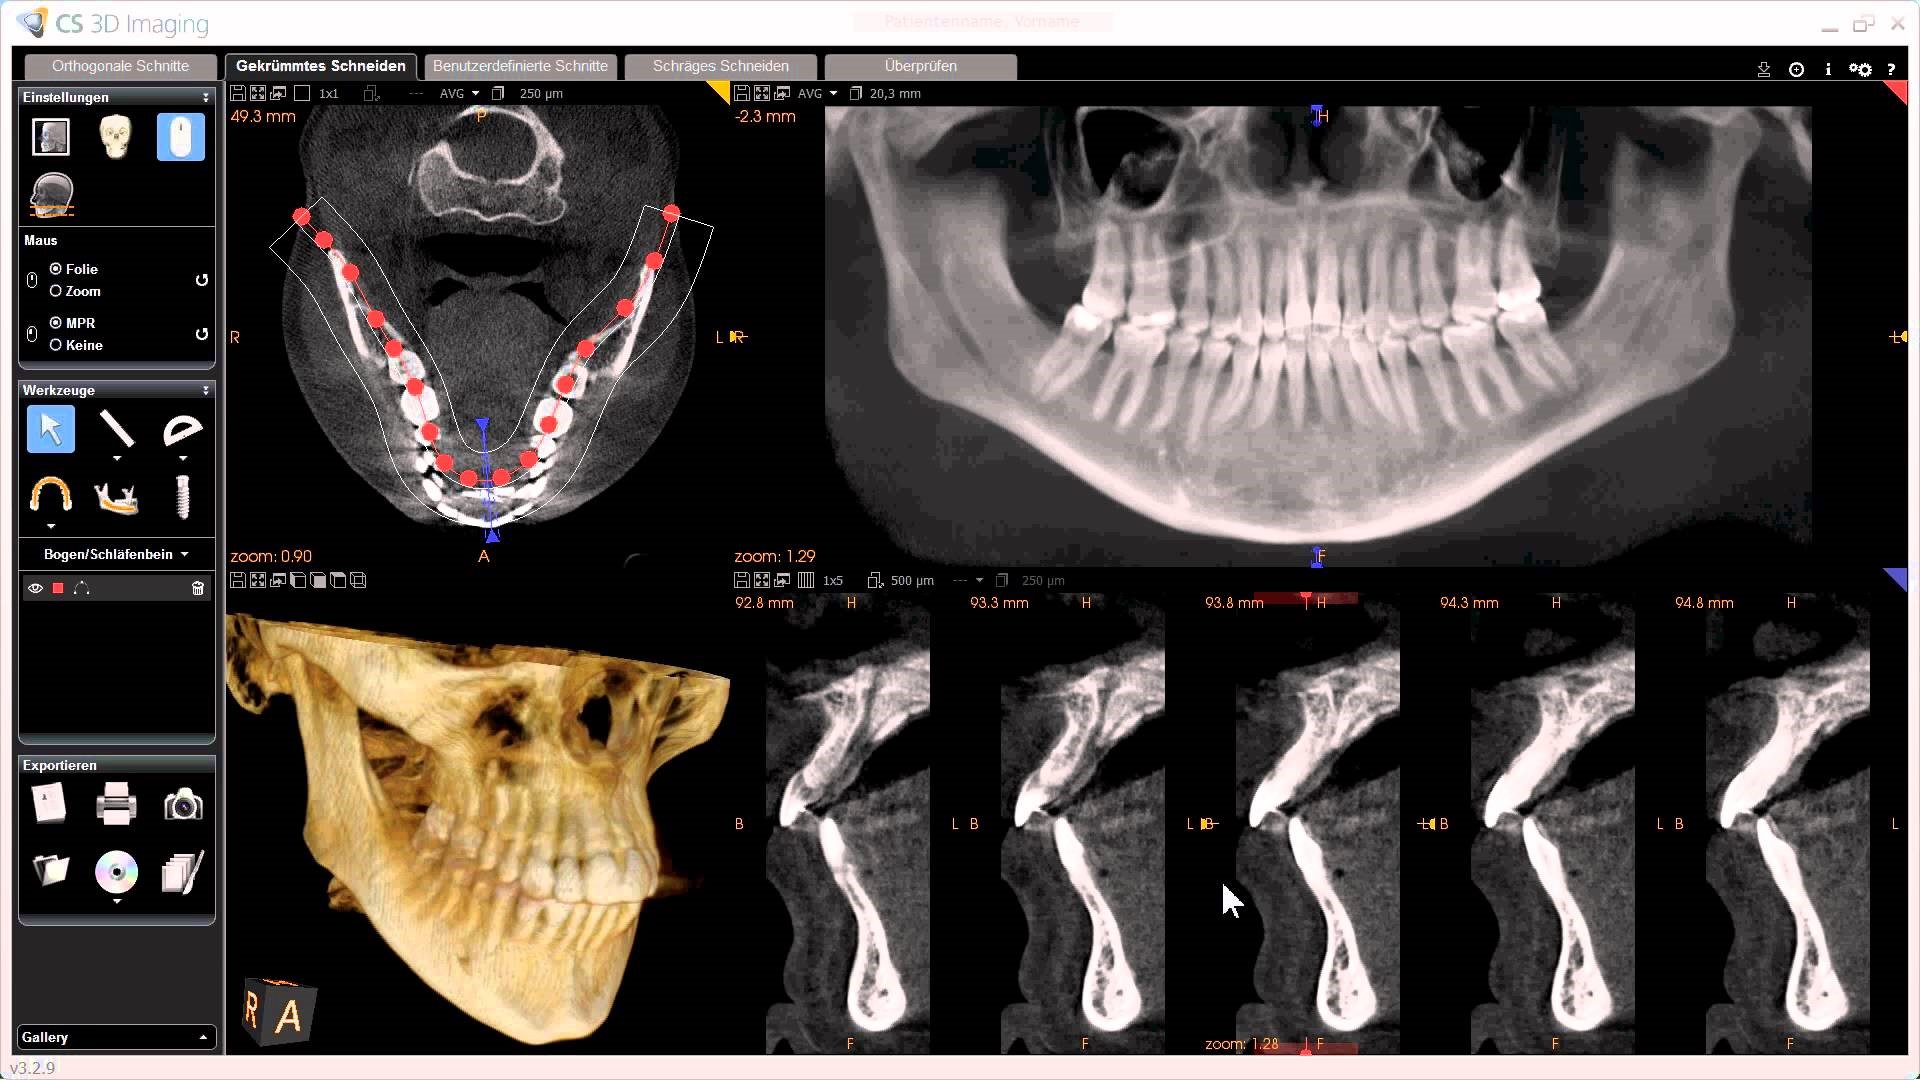

4) कोन बीम सिटीस्कॅन

हा थ्रीडी म्हणजेच त्रिमितीय सिटीस्कॅन असतो. यात आपल्याला हव्या असलेल्या जबड्याच्या भागाची थ्रीडी प्रतिमा मिळते.

दाढ किंवा जबड्यांच्या कठीण सर्जरी किंवा इम्प्लांट साठी अशा सिटीस्कॅन ची गरज पडू शकते.